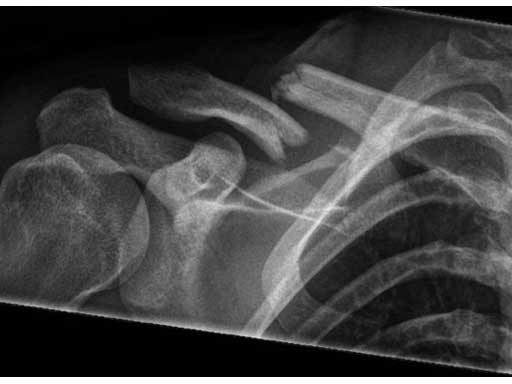

Fig 4ab X-rays 9 months postoperatively.